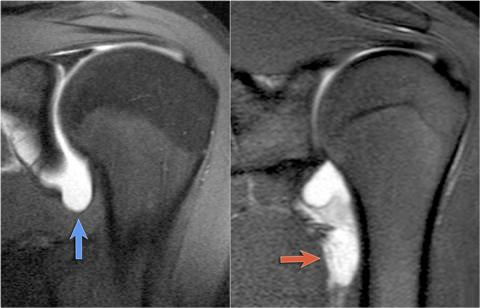

HAGL / GAGL

Humeral Avulsion of the inferior Glenoidal Ligament

- Disruption du IGHL (ligament gléno-huméral inférieur)

- Passage de liquide

- HAGL = Disruption de l’attache humérale

- GAGL = Disruption de la partie Glènoide

Récessus axillaire normal (bleu), vs HAGL (rouge)